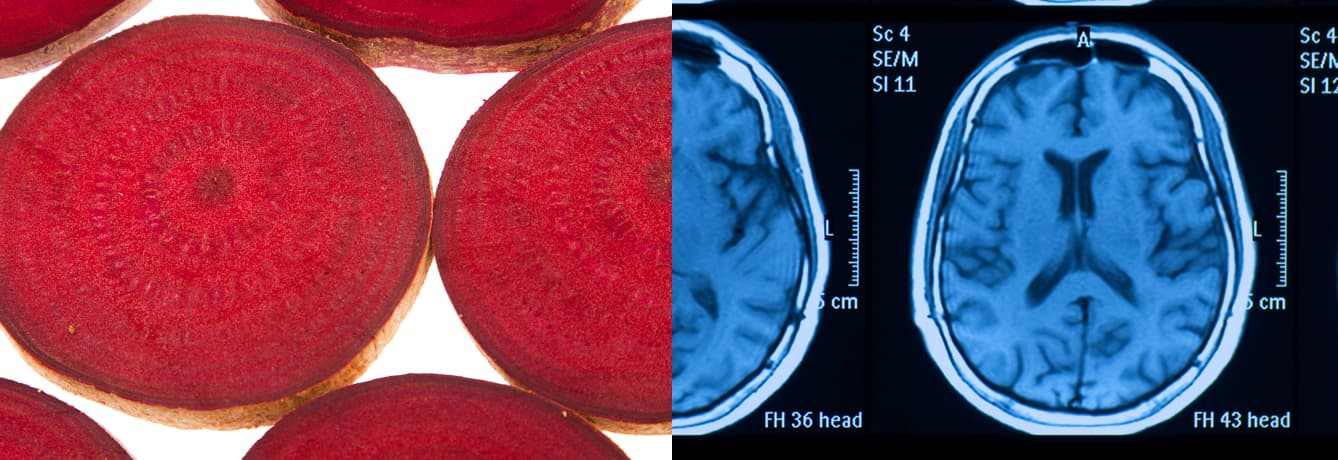

Researchers from Wake Forest University had 14 seniors (70 years old and up) drink either 16 oz. of beet juice or eat a control diet in the morning for two days, then used MRI machines to measure blood flow to the brain. The groups switched diets for another two days, then were tested again. The result: The beet-juice drinkers enjoyed 21% increased blood flow to the frontal lobes — sensitive areas of the brain vulnerable to the degeneration that leads to dementia. “I think these results are consistent and encouraging — that good diet consisting of a lot of fruit and vegetables can contribute to overall health,” said Gary Miller, Ph.D., a senior investigator on the project.